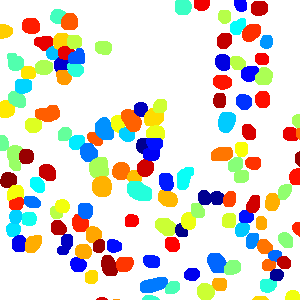

As an essential part of digital pathology, histopathology image analysis is playing increasingly important role in cancer diagnosis, which can provide direct and reliable evidence to diagnose the grade and type of cancer. This paper deals with nuclei segmentation, an important step in histopathological image analysis. The purpose of nuclei semgentation is not only counting the number of nuclei but also obtaining the detailed information of each nucleus. So unlike nuclei detection, here the outputs are the contour of each nucleus instead of only the position of their central points. Hence we can exactly extract each nucleus from the image and make it available for further analysis. For example, the features of the individual nucleus and the distribution of nuclei clusters can be used to grade and classify status of breast cancers [3, 4]. Because of appearance variation such as color, shape, and texture, nuclei segmentation from histopathological images could be very challenging, as illustrated in Fig.1, in which it is very challenging even for human to recognize and segment all nuclei within the images. Fig.1(a) and Fig.1(b) illustrate two histopathological images from different organs. Fig.1(c) and Fig.1(d) are two histopathological images from same organ but have different cancer grade.

Figure 6 shows how our method segments the nuclei step by step. The color variety is well controlled by the color normalization procedure. The prediction result shows clear nuclear areas and nucleus boundaries. In the final segmentation result and ground truth image, each nucleus is represented by a different color.